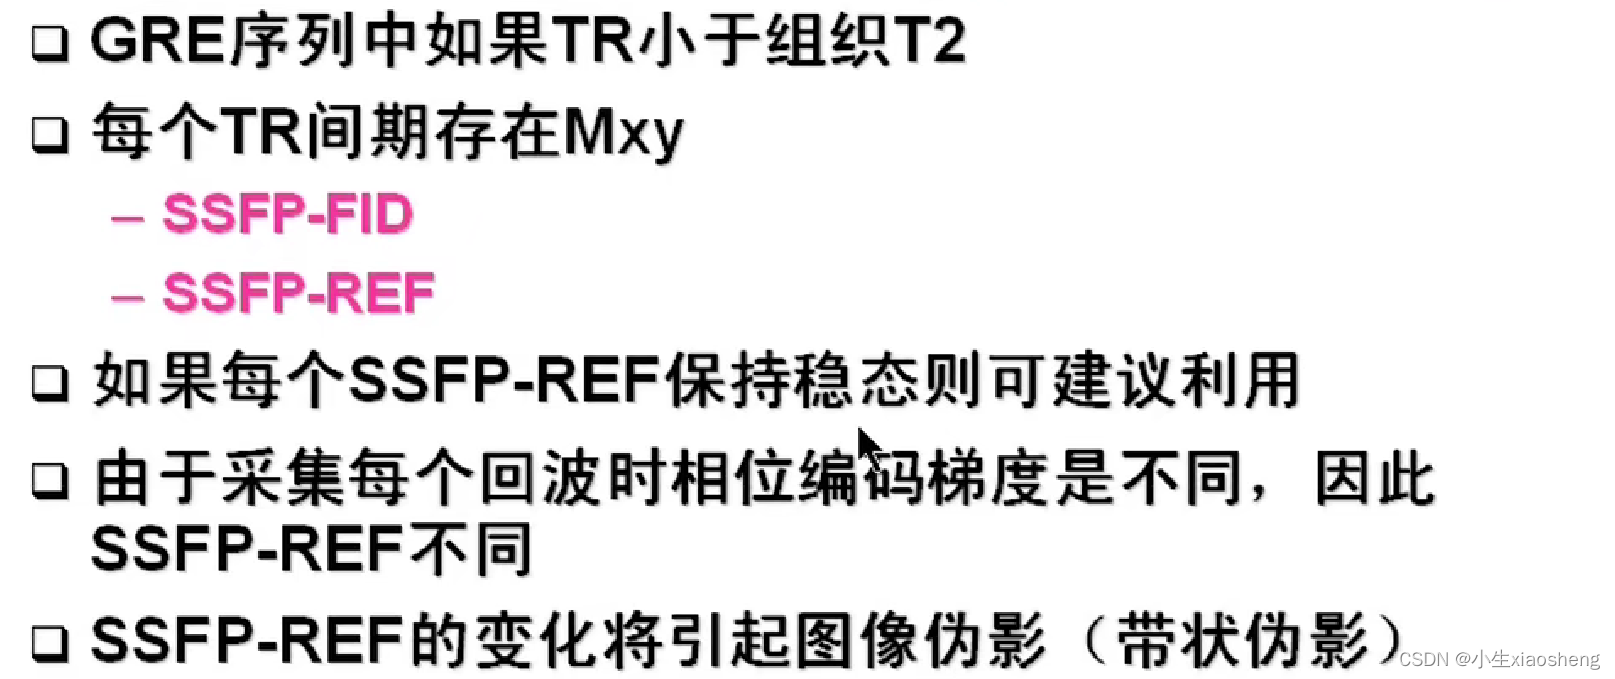

第一次参数的横向脉冲没有全部恢复过来,当第二次脉冲过来时会存在聚焦使得整个脉冲变大,而这个变大的就是SSFP-REF指的是稳态自由进动(Steady-State Free Precession, SSFP)序列中的参考回波(Reference Echo),正常横向的脉冲就叫SSFP-FID。

在SSFP成像中,如果每个SSFP-REF能够保持稳态,那么就可以利用这些回波信号来重建高质量的MRI图像。然而,由于各种因素的影响(如磁场不均匀性、组织特性等),SSFP-REF可能会发生变化,这可能会导致图像伪影(如带状伪影)的出现。而扰相主要用于提高成像速度和消除图像伪影。扰相技术的主要目的是在前一次射频脉冲(α脉冲)的MR信号采集后,对组织中的质子群的相位进行干扰,使其失相位加快,从而消除残留的横向磁化矢量。